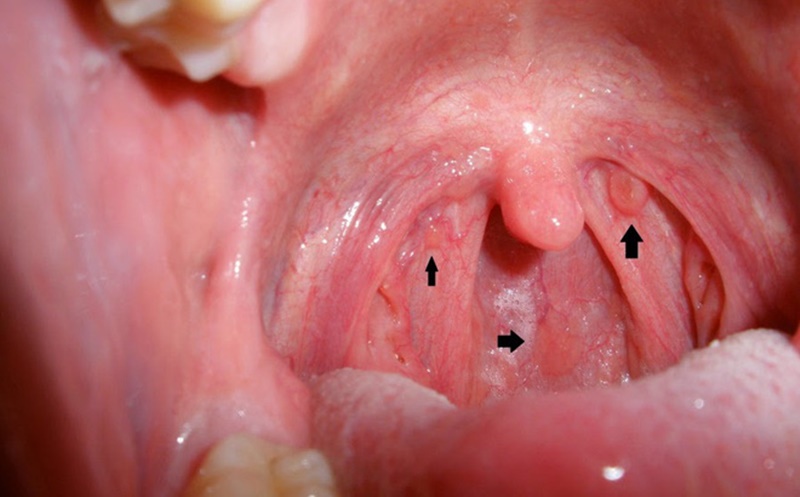

U nhú amidan là một tình trạng y tế phổ biến, xuất hiện dưới dạng một khối u nhỏ và mềm, thường phát triển bất thường gần vùng amidan. Nguyên nhân gây ra u nhú amidan rất đa dạng, từ viêm nhiễm đến tình trạng tổn thương hoặc do sự phát triển không bình thường của mô amidan. Điều này dẫn đến nhiều triệu chứng khác nhau, phức tạp và thường gây ra sự không thoải mái cho người bệnh.

Triệu chứng của u nhú amidan có thể biến đổi từ đau nhức, cảm giác nóng rát, sưng, đỏ, thậm chí là sốt. Một số bệnh nhân có thể cảm thấy cảm giác hơi vướng hoặc cảm thấy khó chịu trong vùng họng mà không hiểu nguyên nhân. Đặc biệt, có trường hợp bệnh nhân không nhận ra triệu chứng này và chỉ phát hiện bệnh khi thực hiện kiểm tra sức khỏe định kỳ hoặc khi triệu chứng trở nên nặng hơn.

U nhú amidan có nhiều nguyên nhân khác nhau và biểu hiện bên ngoài như sau: